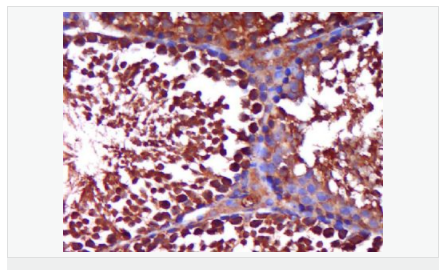

| 產(chǎn)品應(yīng)用 | WB=1:500-2000 ELISA=1:5000-10000 IHC-P=1:100-500 IHC-F=1:100-500 Flow-Cyt=1ug/Test IF=1:100-500 (石蠟切片需做抗原修復(fù)) not yet tested in other applications. optimal dilutions/concentrations should be determined by the end user. |

| 產(chǎn)品介紹 | The androgen receptor gene is more than 90 kb long and codes for a protein that has 3 major functional domains: the N-terminal domain, DNA-binding domain, and androgen-binding domain. The protein functions as a steroid-hormone activated transcription factor. Upon binding the hormone ligand, the receptor dissociates from accessory proteins, translocates into the nucleus, dimerizes, and then stimulates transcription of androgen responsive genes. This gene contains 2 polymorphic trinucleotide repeat segments that encode polyglutamine and polyglycine tracts in the N-terminal transactivation domain of its protein. Expansion of the polyglutamine tract causes spinal bulbar muscular atrophy (Kennedy disease). Mutations in this gene are also associated with complete androgen insensitivity (CAIS). Two alternatively spliced variants encoding distinct isoforms have been described. [provided by RefSeq, Jul 2008] Function: Steroid hormone receptors are ligand-activated transcription factors that regulate eukaryotic gene expression and affect cellular proliferation and differentiation in target tissues. Transcription factor activity is modulated by bound coactivator and corepressor proteins. Transcription activation is down-regulated by NR0B2. Activated, but not phosphorylated, by HIPK3 and ZIPK/DAPK3. [ENZYME REGULATION] AIM-100 (4-amino-5,6-biaryl-furo[2,3-d]pyrimidine) suppresses TNK2-mediated phosphorylation at Tyr-267. Inhibits the binding of the Tyr-267 phosphorylated form to androgen-responsive enhancers (AREs) and its transcriptional activity. Subunit: Binds DNA as a homodimer. Part of a ternary complex containing AR, EFCAB6/DJBP and PARK7. Interacts with HIPK3 and NR0B2 in the presence of androgen. The ligand binding domain interacts with KAT7/HBO1 in the presence of dihydrotestosterone. Interacts with EFCAB6/DJBP, PELP1, PQBP1, RANBP9, RBAK, SPDEF, SRA1, TGFB1I1, ZNF318 and RREB1. Interacts with ZMIZ1/ZIMP10 and ZMIZ2/ZMIP7 which both enhance its transactivation activity. Interacts with SLC30A9 and RAD54L2/ARIP4. Interacts via the ligand-binding domain with LXXLL and FXXLF motifs from NCOA1, NCOA2, NCOA3, NCOA4 and MAGEA11. The AR N-terminal poly-Gln region binds Ran resulting in enhancement of AR-mediated transactivation. Ran-binding decreases as the poly-Gln length increases. Interacts with HIP1 (via coiled coil domain). Interacts (via ligand-binding domain) with TRIM68. Interacts with TNK2. Interacts with USP26. Interacts with RNF6. Interacts (regulated by RNF6 probably through polyubiquitination) with RNF14; regulates AR transcriptional activity. Interacts with PRMT2 and TRIM24. Interacts with GNB2L1/RACK1. Interacts with RANBP10; this interaction enhances dihydrotestosterone-induced AR transcriptional activity. Interacts with PRPF6 in a hormone-independent way; this interaction enhances dihydrotestosterone-induced AR transcriptional activity. Interacts with STK4/MST1. Interacts with ZIPK/DAPK3. Interacts with LPXN. Interacts with MAK. Part of a complex containing AR, MAK and NCOA3. Subcellular Location: Nucleus. Cytoplasm. Note=Predominantly cytoplasmic in unligated form but translocates to the nucleus upon ligand-binding. Can also translocate to the nucleus in unligated form in the presence of GNB2L1. Tissue Specificity: Isoform 2 is mainly expressed in heart and skeletal muscle. Post-translational modifications: Sumoylated on Lys-386 (major) and Lys-520. Ubiquitinated. Deubiquitinated by USP26. 'Lys-6' and 'Lys-27'-linked polyubiquitination by RNF6 modulates AR transcriptional activity and specificity. Phosphorylated in prostate cancer cells in response to several growth factors including EGF. Phosphorylation is induced by c-Src kinase (CSK). Tyr-534 is one of the major phosphorylation sites and an increase in phosphorylation and Src kinase activity is associated with prostate cancer progression. Phosphorylation by TNK2 enhances the DNA-binding and transcriptional activity and may be responsible for androgen-independent progression of prostate cancer. Phosphorylation at Ser-81 by CDK9 regulates AR promoter selectivity and cell growth. Phosphorylation by PAK6 leads to AR-mediated transcription inhibition. Palmitoylated by ZDHHC7 and ZDHHC21. Palmitoylation is required for plasma membrane targeting and for rapid intracellular signaling via ERK and AKT kinases and cAMP generation. DISEASE: Defects in AR are the cause of androgen insensitivity syndrome (AIS) [MIM:300068]; previously known as testicular feminization syndrome (TFM). AIS is an X-linked recessive form of pseudohermaphroditism due end-organ resistance to androgen. Affected males have female external genitalia, female breast development, blind vagina, absent uterus and female adnexa, and abdominal or inguinal testes, despite a normal 46,XY karyotype. Defects in AR are the cause of spinal and bulbar muscular atrophy X-linked type 1 (SMAX1) [MIM:313200]; also known as Kennedy disease. SMAX1 is an X-linked recessive form of spinal muscular atrophy. Spinal muscular atrophy refers to a group of neuromuscular disorders characterized by degeneration of the anterior horn cells of the spinal cord, leading to symmetrical muscle weakness and atrophy. SMAX1 occurs only in men. Age at onset is usually in the third to fifth decade of life, but earlier involvement has been reported. It is characterized by slowly progressive limb and bulbar muscle weakness with fasciculations, muscle atrophy, and gynecomastia. The disorder is clinically similar to classic forms of autosomal spinal muscular atrophy. Note=Caused by trinucleotide CAG repeat expansion. In SMAX1 patients the number of Gln ranges from 38 to 62. Longer expansions result in earlier onset and more severe clinical manifestations of the disease. Note=Defects in AR may play a role in metastatic prostate cancer. The mutated receptor stimulates prostate growth and metastases development despite of androgen ablation. This treatment can reduce primary and metastatic lesions probably by inducing apoptosis of tumor cells when they express the wild-type receptor. Defects in AR are the cause of androgen insensitivity syndrome partial (PAIS) [MIM:312300]; also known as Reifenstein syndrome. PAIS is characterized by hypospadias, hypogonadism, gynecomastia, genital ambiguity, normal XY karyotype, and a pedigree pattern consistent with X-linked recessive inheritance. Some patients present azoospermia or severe oligospermia without other clinical manifestations. Similarity: Belongs to the nuclear hormone receptor family. NR3 subfamily. Contains 1 nuclear receptor DNA-binding domain. SWISS: P10275 Gene ID: 367 Database links: Entrez Gene: 367 Human Entrez Gene: 11835 Mouse Omim: 313700 Human SwissProt: P10275 Human SwissProt: P19091 Mouse Unigene: 496240 Human Unigene: 39005 Mouse Unigene: 394224 Mouse Unigene: 439657 Mouse Unigene: 9813 Rat Important Note: This product as supplied is intended for research use only, not for use in human, therapeutic or diagnostic applications. AR是一個(gè)由917個(gè)氨基酸組成的蛋白質(zhì),位于雄激素靶組織細(xì)胞中或細(xì)胞表面上的特異分子部位或結(jié)構(gòu)。 AR在前列腺癌中起著重要的作用,研究表明AR的表達(dá)與組織分型形成一定的相關(guān)性 ,AR在高分化的腫瘤中表達(dá)較多,而在低分化的腫瘤中表達(dá)較少。用于前列腺癌的檢測(cè),指導(dǎo)臨床治療,目前可用于乳腺癌、食道癌等各項(xiàng)腫瘤的研究。 |